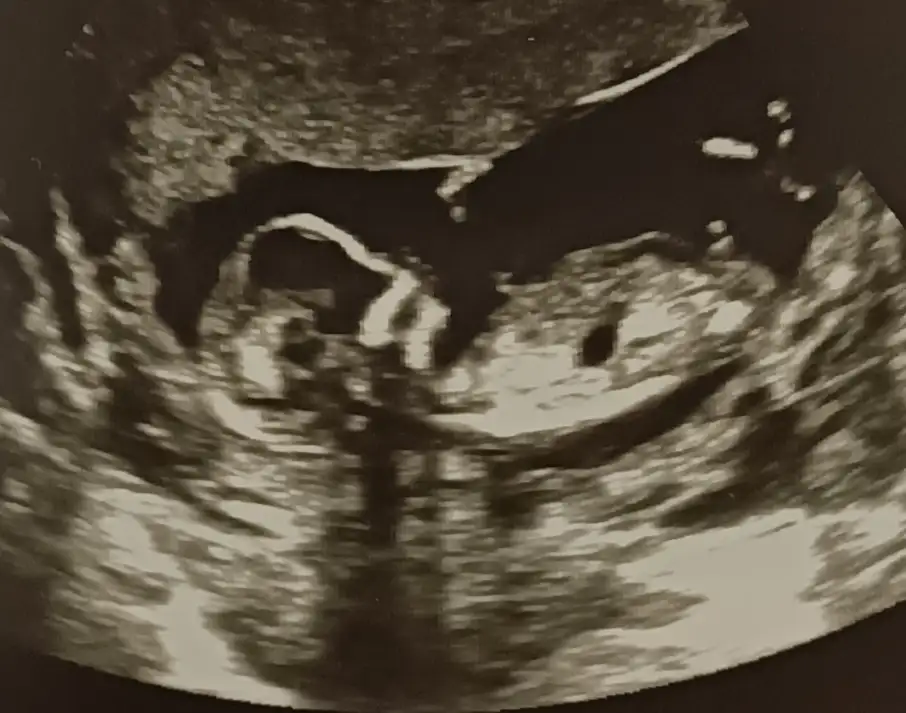

Sanki sanki diyerek kız gibi gibi tekrar USG paylasinBana da yorum yapabilir misiniz @İkra meyra. Ultrason cihazı biraz kötüydü ama 11 haftalık

Sanki erkek tekrar USG paylasinBana da yorum yapabilir misiniz @İkra meyra. Ultrason cihazı biraz kötüydü ama 11 haftalık

Kaç haftalık büyük sanki USG 11 12 13 haftalar olmalı sanki sanki kız gibi tekrar USG paylasinBana da tahminde bulunabilir misiniz acaba